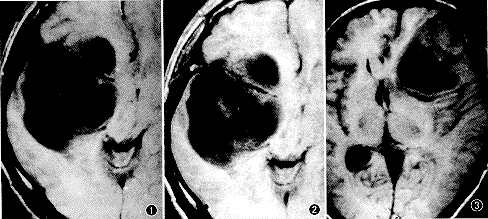

图1 右颞额星形胶质细胞瘤Ⅰ级(囊性型)。横断面平扫T1WI示病灶呈均匀低信号,边界清楚,轻度占位征象

图2 与图1同一病人,增强后T1WI示病灶无强化,肿瘤跨叶生长

图3 左额叶星形胶质细胞瘤Ⅱ级(实质性伴囊变型)。横断面T1WI示病灶呈低、等混合信号,且累及皮层,灶周环绕低信号带,病理证实为包膜

图4 与图3为同一病人,横断面T2WI示病灶呈高信号,灶周见高信号水肿区,包膜仍呈低信号

图5 左颞顶星形胶质细胞瘤Ⅲ级(实质性伴出血)。横断面T1WI示病灶呈等、高信号,灶内片状高信号为出血,重度占位征象

图6 与图5同一病人,横断面T2WI示病灶呈高、等混合信号,瘤周水肿明显,肿瘤前缘低信号影为流空的肿瘤血管

图7 左颞星形胶质细胞瘤Ⅳ级(实质性伴坏死)。横断面T1WI示病灶呈类圆形略低信号,瘤周环绕低信号带为假包膜

图8 与图7同一病人,增强后横断面T1WI示病灶呈不规则环形强化,病理证实为假包膜区,中心为无强化坏死区